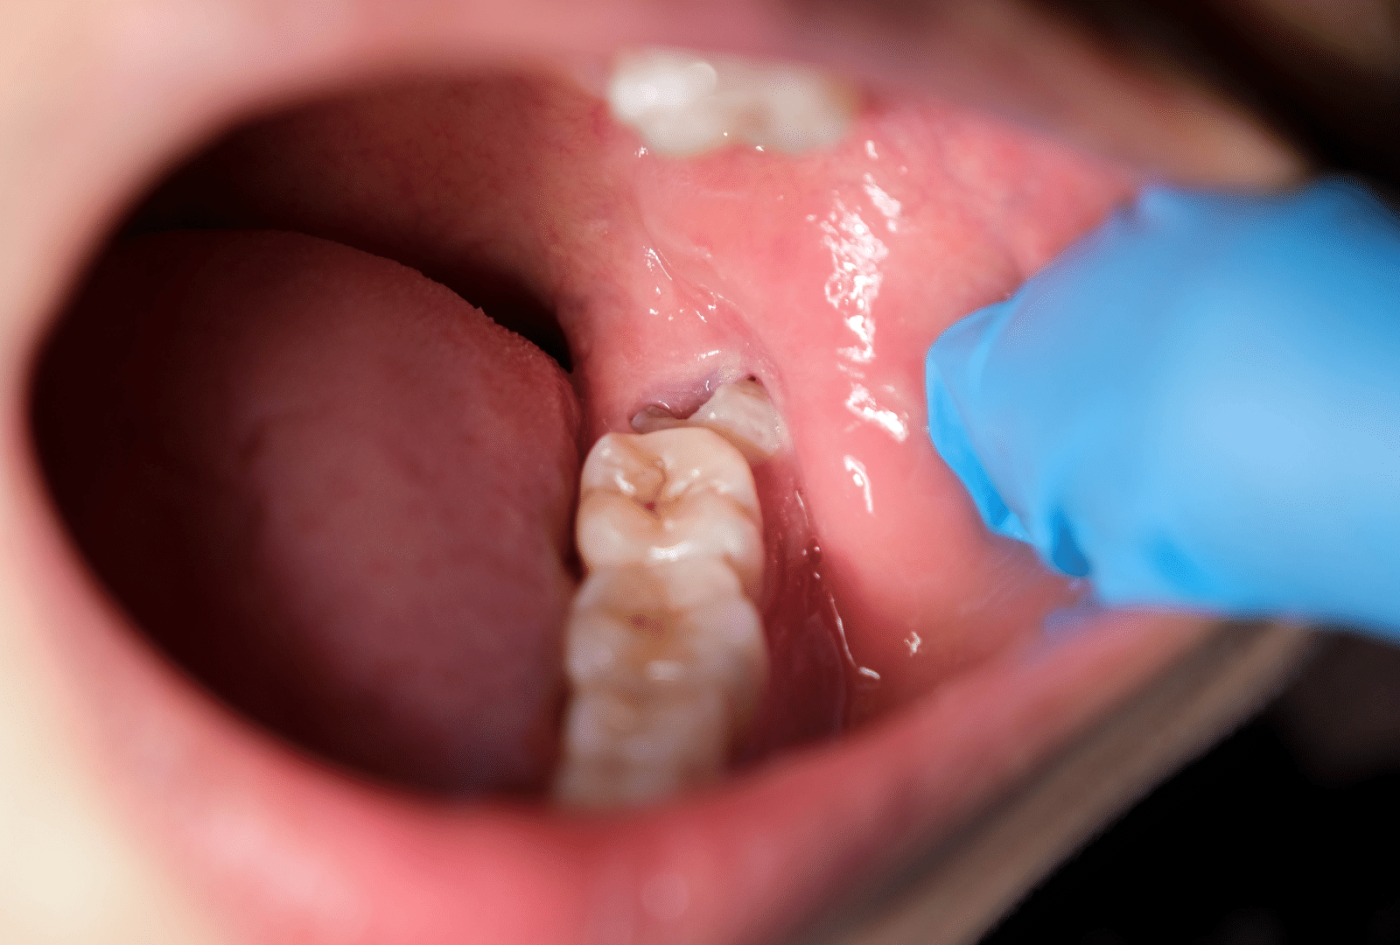

Dry Socket – The Complication to Watch For

Dry socket (alveolar osteitis) occurs when the blood clot is dislodged or dissolves prematurely, exposing the underlying bone. It affects roughly 2-5% of extractions but up to 30% of lower wisdom tooth removals.

Symptoms:

- Severe, throbbing pain that begins 2-4 days after surgery (after initial improvement)

- Pain radiating to the ear or jaw

- Empty-looking socket with visible bone

- Bad taste or smell

If you suspect dry socket, return to your dentist or oral surgeon. Treatment involves cleaning and packing the socket with a medicated dressing – relief is usually rapid.

Risk factors: Smoking, birth control pills, poor clot formation, aggressive rinsing.